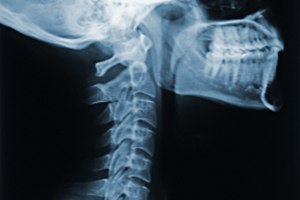

Neck pain ranks as one of the most common painful disorders out there. At least 15% of the population is affected by it, and it occurs more frequently in women than men and in middle-age individuals. Neck pain can restrict movement and interfere with normal activities, making it a burden to many of those affected by it. In some cases, problems with the neck can lead to what's called a cervicogenic headache, which means the neck issues need to be addressed to fix it. There are several different strategies for treating neck pain and other disorders, but most consist of various types of exercises to improve flexibility and increase strength in the region. Although these exercises are commonly used to treat neck pain, some recent studies have only found low-quality evidence to support their use. For this reason, stronger evidence is needed to more firmly recommend different types of exercise for neck disorders. Researchers, therefore, decided to conduct a Cochrane review on the topic. Cochrane reviews collect all the highest-quality research available in order to provide guidance for treatment, and this particular review focused on the effectiveness of different types of exercise for neck disorders.